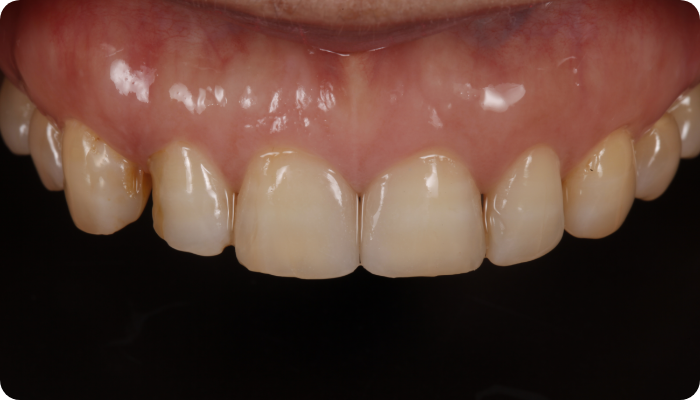

우리 얼굴에서 미소는 첫인상을 좌우합니다. 이런 좋은 인상을 위해 라미네이트를 고려 중이시라면,

많은 것들을 고려해야 합니다. 라미네이트 시 무조건 하얗고, 얇기만 한 치아가 좋은 것은 아닙니다.

개개인의 얼굴마다 비율에 맞게 이상적인 치아의 형태가 있습니다.

그저 예쁘기만한 부자연스러운 라미네이트가 아닙니다.

더서울치과의원은 각 개인의 얼굴 특성에 맞는 맞춤형 라미네이트를 선물합니다.